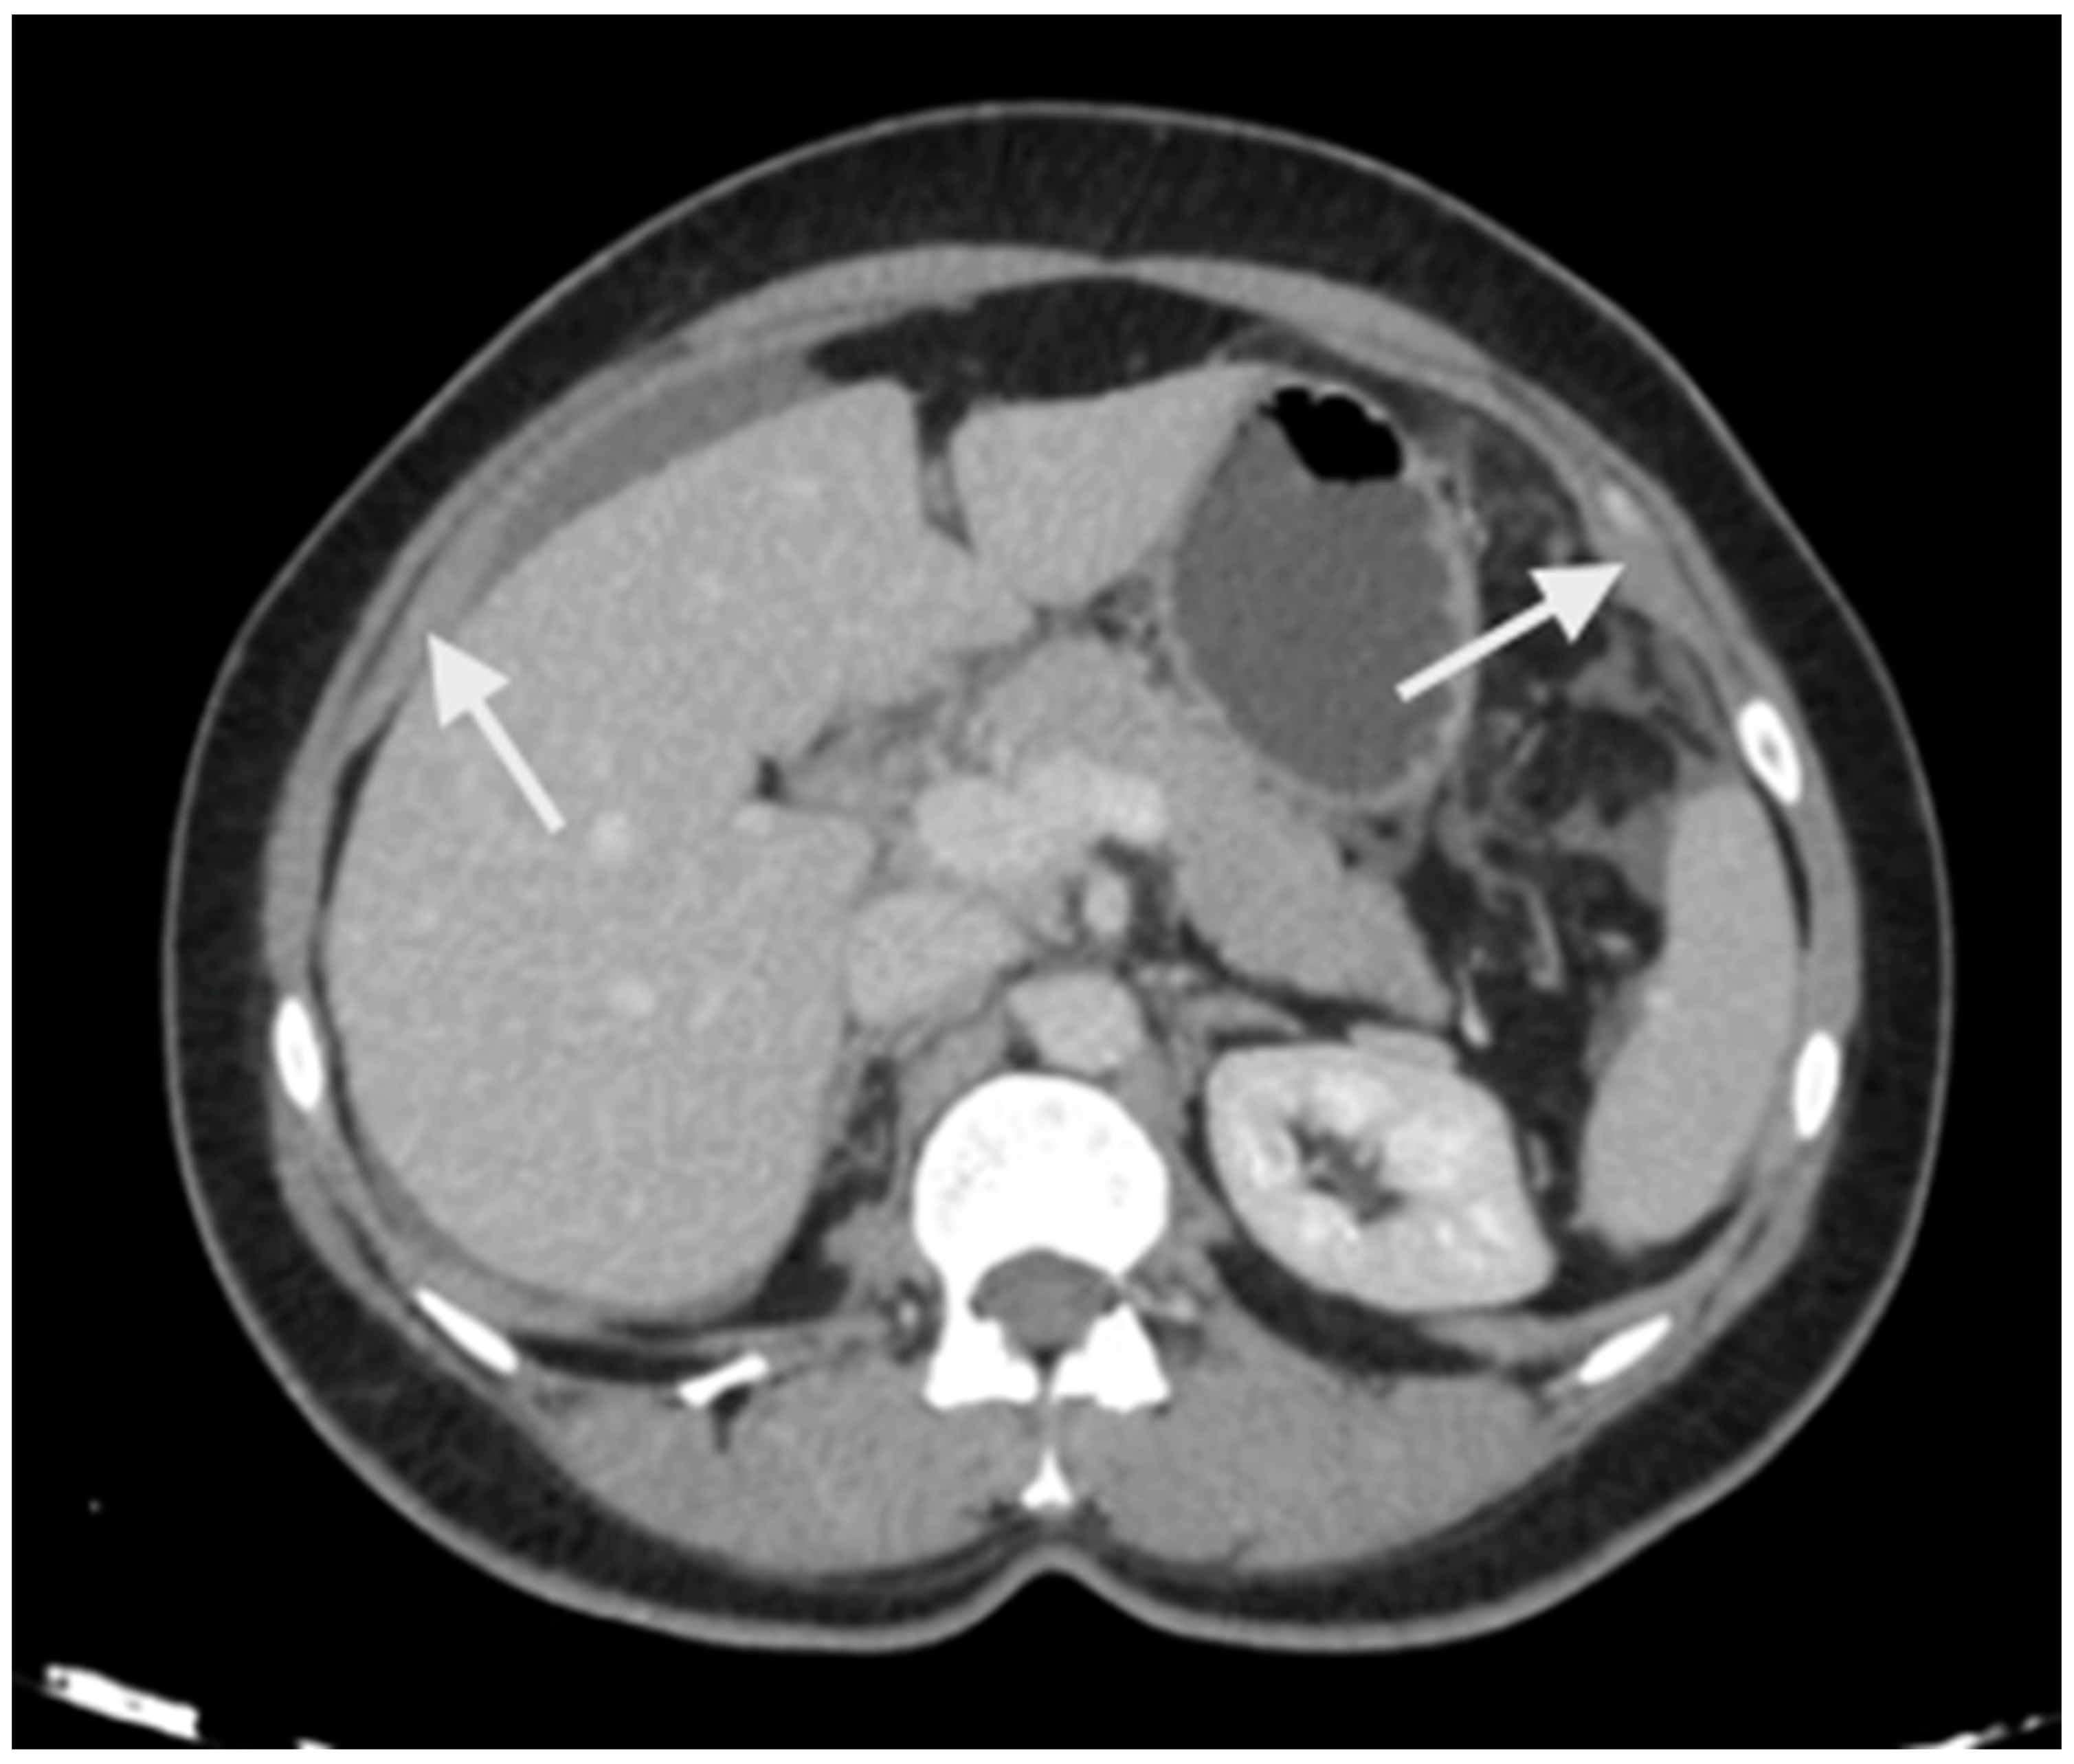

Imaging has two significant roles: the first is the detection of limited disease and all sites of disease in the upper abdomen, and the second is predicting resectability. The most common study is a contrast-enhanced CT scan of the thorax, abdomen, and pelvis [47]. Several investigators have shown that a CT scan underestimates the extent of peritoneal disease [48,49,50]. The spread of peritoneal disease is usually reported using the peritoneal cancer index (PCI). The accuracy in predicting the extent of upper-abdominal disease is not studied separately; the overall accuracy ranges from 15 to 80% [48,49,50]. Peritoneal disease can present as a thickening and/or enhancement of the parietal peritoneum (the subphrenic peritoneum) or discrete nodular deposits (Figure 1).

Figure 1.

Peritoneal thickening and enhancement (white arrows) as seen on a contrast-enhanced CT scan suggestive of the presence of disease.